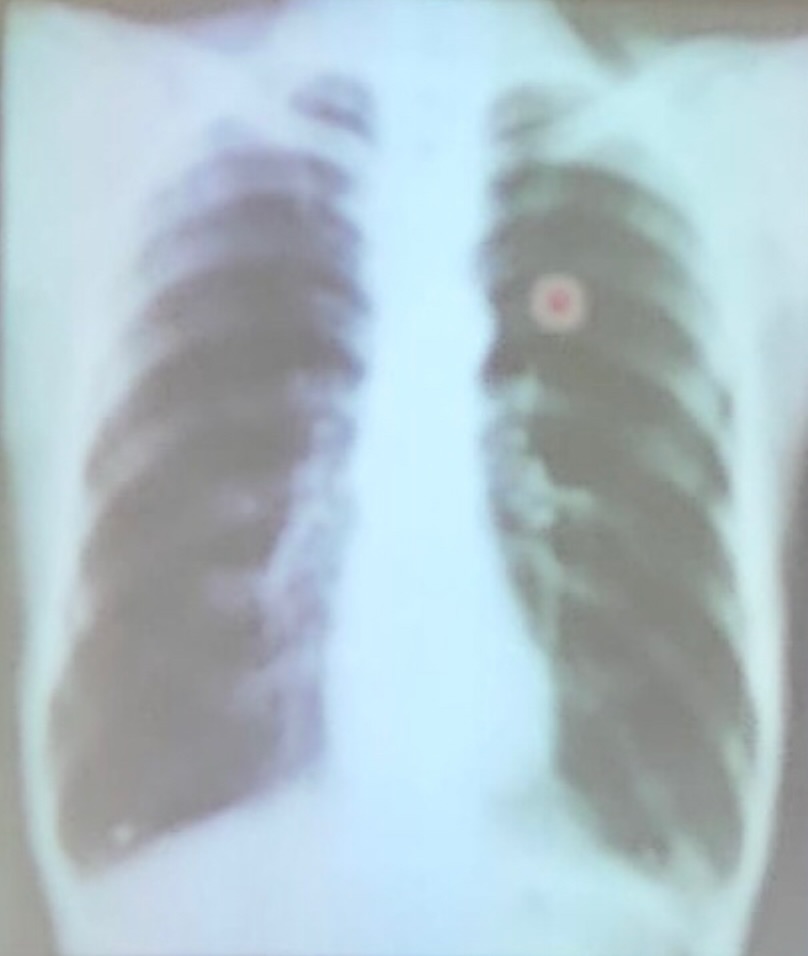

enfisema